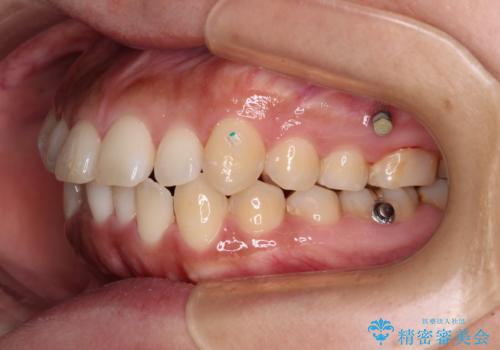

インビザライン単体での治療ではなく、カリエール・ディスタライザーという補助装置を併用して、より確実性を上げることとしました。

補助装置で八重歯を解消しながら、並行してインビザラインで歯列を整えることとしました。

カリエールディスタライザーを併用したことで、すっきりとした口元になり、上下の正中を合わせることができました。